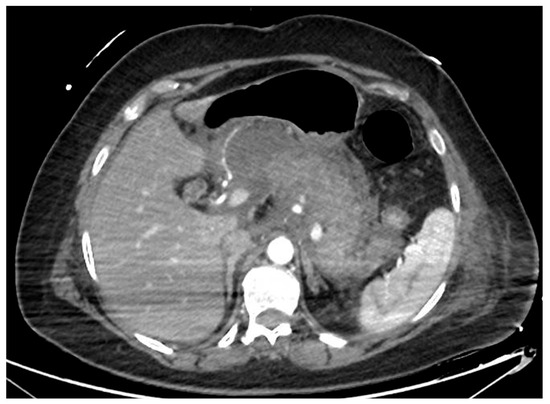

Acute pancreatitis is one of the most common causes of hospitalization among gastroenterological diseases and accounts for relevant expenses for the healthcare system [1,2]. In 5–10% of cases, the acute inflammatory process leads to necrosis of the pancreatic parenchyma and/or peripancreatic tissue (Figure 1). Necrotizing pancreatitis has usually a more severe clinical course, more frequent local and systemic complications, organ failure, need for interventions and higher mortality rates [3]. According to the Atlanta classification, peripancreatic collections are classified depending on the timing from the acute onset of pancreatitis (Table 1). After 4 weeks, collections usually have definite limits and mature walls, and are called pseudocysts or walled-off necrosis (WON), depending on the absence or presence of solid necrotic material. Endoscopic drainage and debridement (i.e., endoscopic necrosectomy, EN) have gained great popularity for the management of WON, in light of its less invasive nature compared to percutaneous or surgical interventions, together with a high clinical efficacy. In this review, we will summarize the evidence available regarding the indication, timing and technique of endoscopic management of WON, including indication and technique of EN, and we will discuss some unresolved issues and future perspectives in this field.

Figure 1.

CT scan image of a necrotizing pancreatitis, with hypoenhancing areas of pancreatic parenchyma. CT, computed tomography.